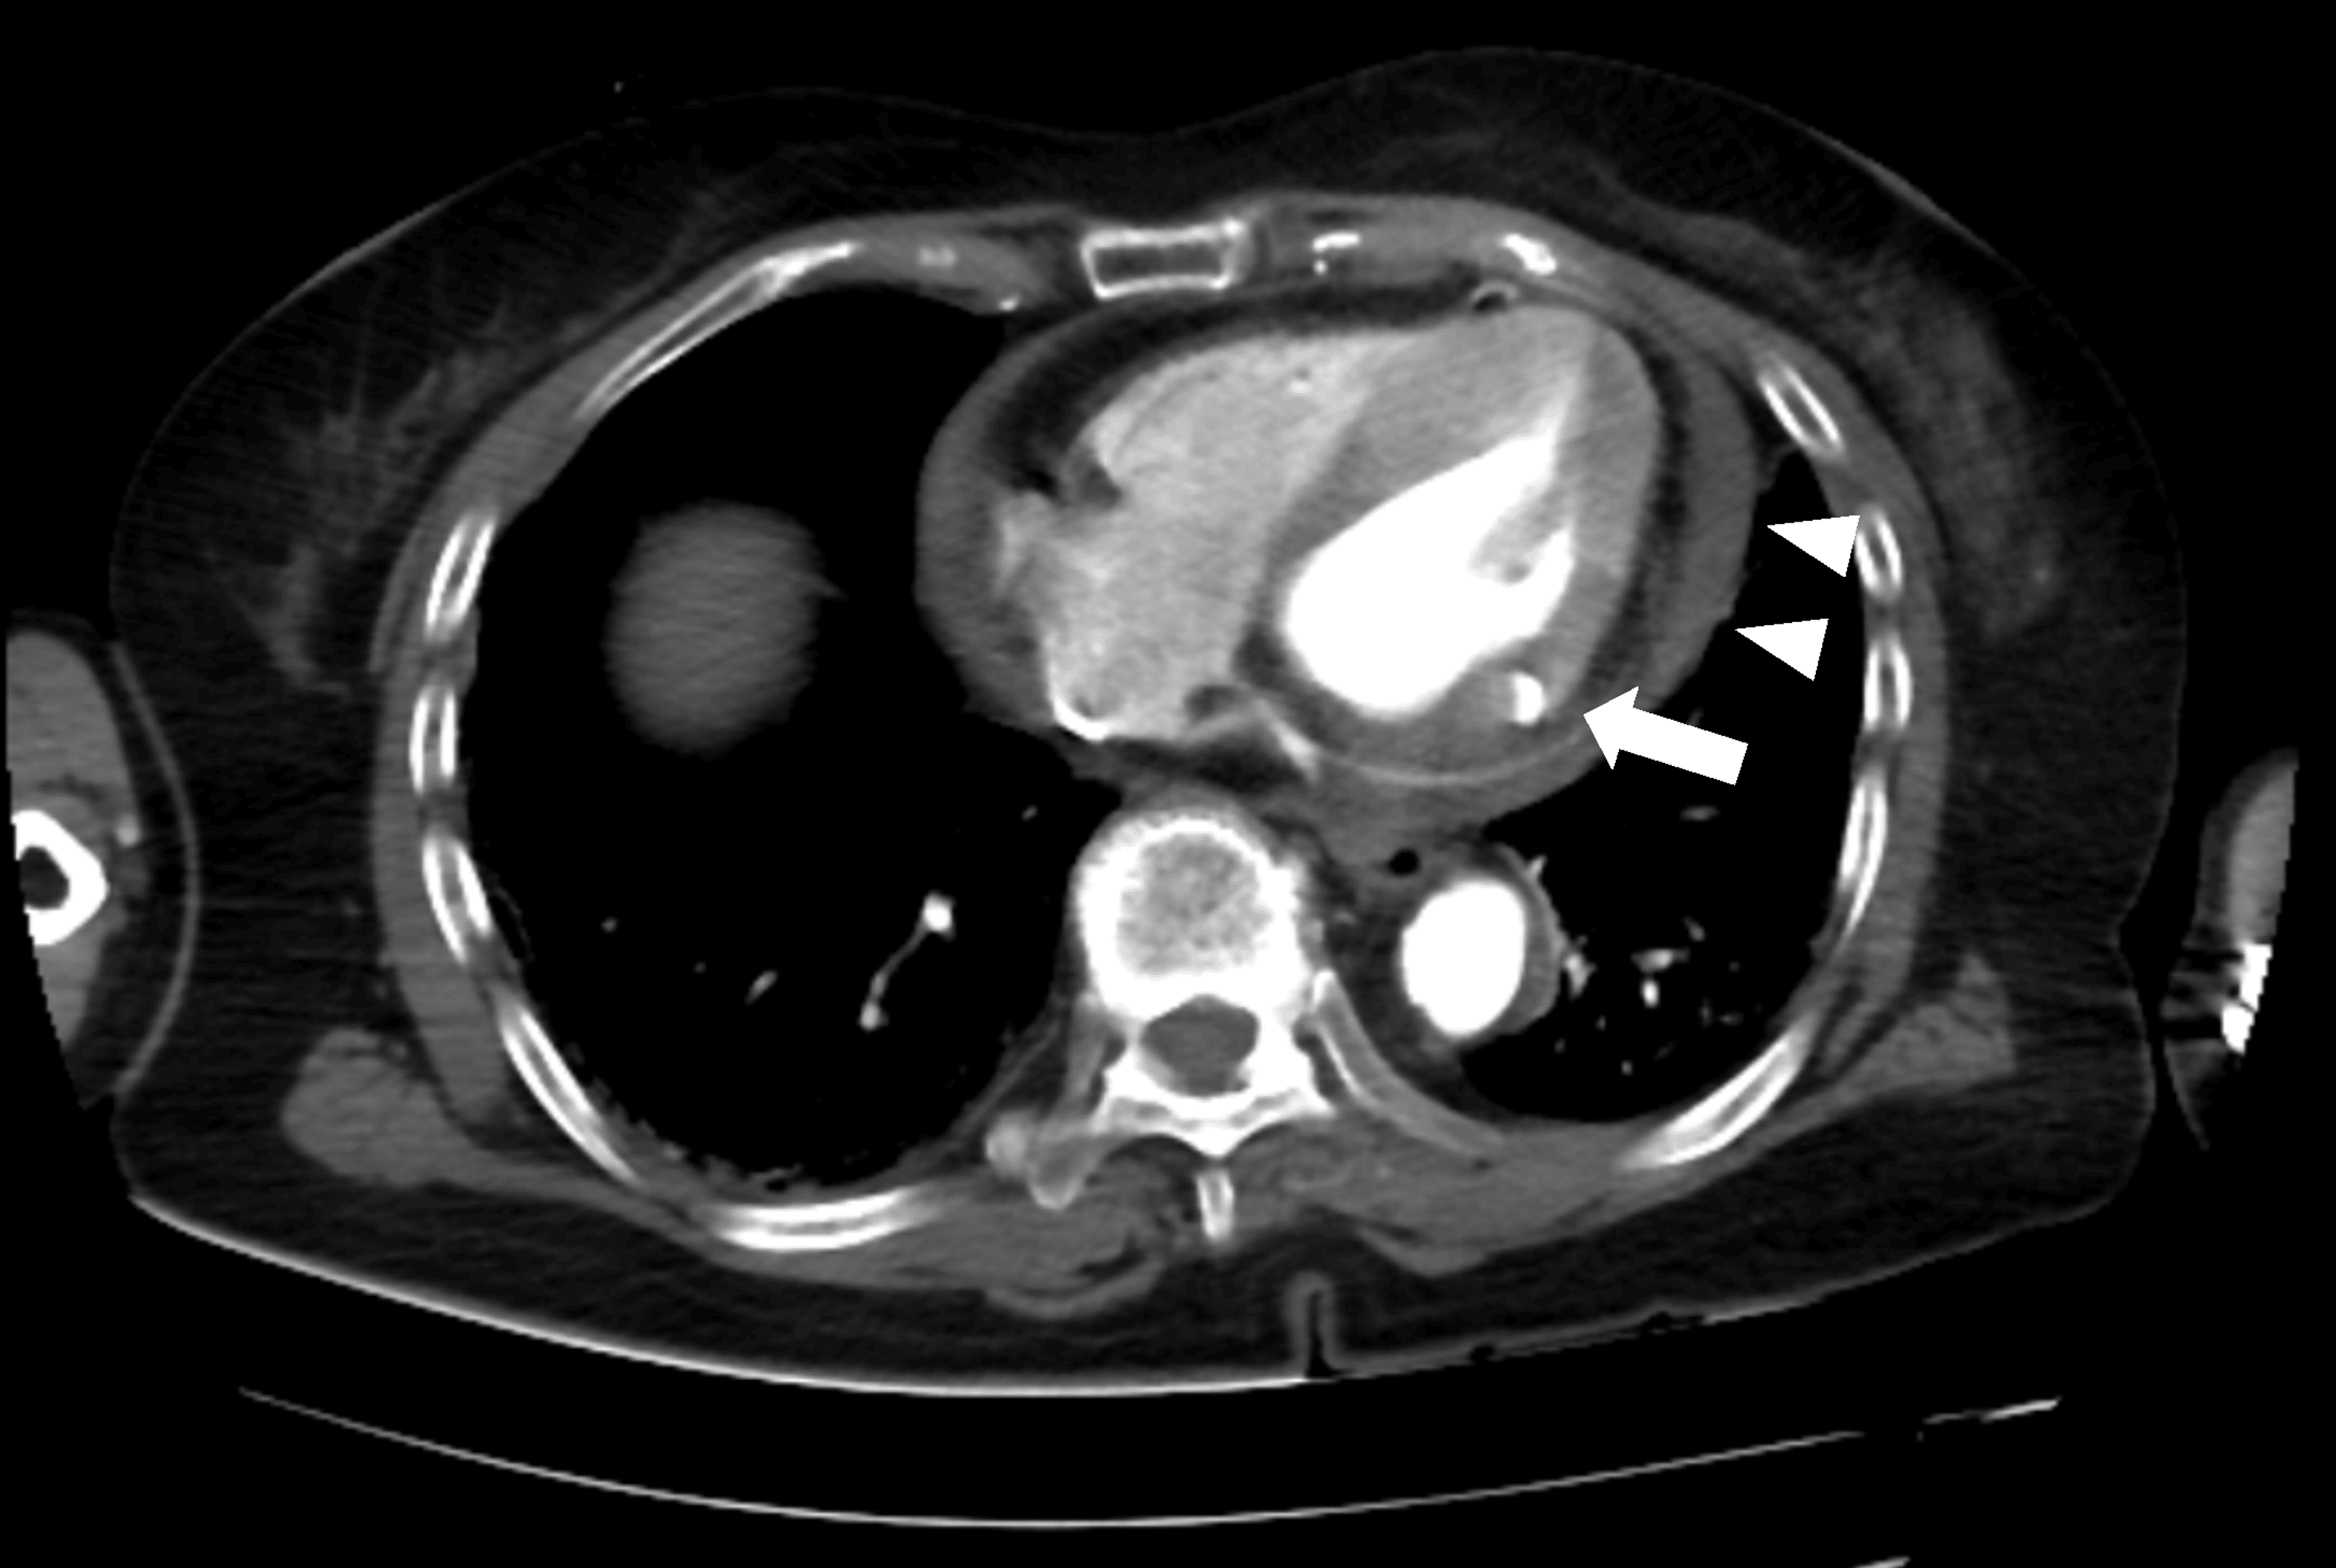

Case Report Free Wall Rupture . Without cardiac surgery, 94% of patients with left ventricular free wall rupture (lvfwr) due to tcm die. Pericardiocentesis revealed hemopericardium, and multidetector computed tomography angiography showed left ventricular free wall rupture. Here we present a case of a patient who suffered a left ventricular free wall rupture as a mechanical complication of myocardial. Through our case we highlight the. Left ventricular (lv) free wall ruptures (lvfwrs) of myocardial infarctions (mis) are still one of the most fatal mechanical complications. We are presenting the case of a 58 years old male with left ventricular free wall rupture occurred.

We are presenting the case of a 58 years old male with left ventricular free wall rupture occurred. Pericardiocentesis revealed hemopericardium, and multidetector computed tomography angiography showed left ventricular free wall rupture. Left ventricular (lv) free wall ruptures (lvfwrs) of myocardial infarctions (mis) are still one of the most fatal mechanical complications. Here we present a case of a patient who suffered a left ventricular free wall rupture as a mechanical complication of myocardial. Without cardiac surgery, 94% of patients with left ventricular free wall rupture (lvfwr) due to tcm die. Through our case we highlight the.

Case Report Free Wall Rupture Left ventricular (lv) free wall ruptures (lvfwrs) of myocardial infarctions (mis) are still one of the most fatal mechanical complications. We are presenting the case of a 58 years old male with left ventricular free wall rupture occurred. Here we present a case of a patient who suffered a left ventricular free wall rupture as a mechanical complication of myocardial. Without cardiac surgery, 94% of patients with left ventricular free wall rupture (lvfwr) due to tcm die. Through our case we highlight the. Left ventricular (lv) free wall ruptures (lvfwrs) of myocardial infarctions (mis) are still one of the most fatal mechanical complications. Pericardiocentesis revealed hemopericardium, and multidetector computed tomography angiography showed left ventricular free wall rupture.

Postinfarction Left Ventricular Free Wall Rupture Diagnosed by ContrastEnhanced Computed Case Report Free Wall Rupture Left ventricular (lv) free wall ruptures (lvfwrs) of myocardial infarctions (mis) are still one of the most fatal mechanical complications. Pericardiocentesis revealed hemopericardium, and multidetector computed tomography angiography showed left ventricular free wall rupture. Here we present a case of a patient who suffered a left ventricular free wall rupture as a mechanical complication of myocardial. Through our case we. Case Report Free Wall Rupture.

Postinfarction Left Ventricular Free Wall Rupture Diagnosed by ContrastEnhanced Computed Case Report Free Wall Rupture Left ventricular (lv) free wall ruptures (lvfwrs) of myocardial infarctions (mis) are still one of the most fatal mechanical complications. Pericardiocentesis revealed hemopericardium, and multidetector computed tomography angiography showed left ventricular free wall rupture. Without cardiac surgery, 94% of patients with left ventricular free wall rupture (lvfwr) due to tcm die. Here we present a case of a patient who. Case Report Free Wall Rupture.